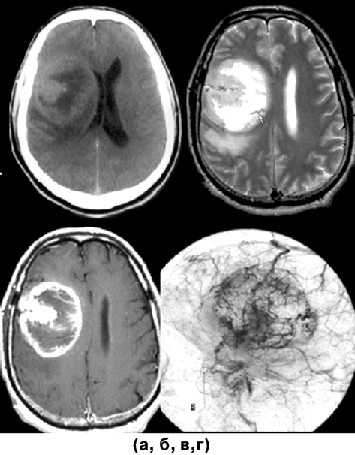

Для доброкачественных диффузных астроцитом при КТ наиболее характерна зона понижения плотности, не имеющая четких границ с окружающим мозговым веществом (рис. 1а, г). Внутривенное введение контрастного вещества обычно не приводит к повышению рентгеновской плотности очага. Разрешающая способность КТ недостаточна для идентификации границ опухоли, особенно изоплотностной по отношению к мозговому веществу.

МРТ — более точный метод визуализации астроцитом. Доброкачественные астроцитомы представляются изо— или гипоинтенсивными на Т1-взвешенных изображениях (рис. 1б, д). В режиме Т2, наиболее информативном при данной патологии, эти опухоли могут выглядеть как сравнительно хорошо отграниченная зона гомогенно повышенного сигнала (рис. 1в, е). “Масс-эффект” выражен, как правило, незначительно, контраст накапливается редко. Так как эти опухоли обычно диагностируются только на стадии выраженных клинических проявлений, для них типично поражение одновременно нескольких долей мозга. Перифокальный отек не характерен.

Рисунок 1. Астроцитомы:

а — астроцитома левой заднелобной области (КТ с контрастным усилением); б — астроцитома левой заднелобной области (МРТ, Т1-взвешенные изображения); в — астроцитома левой заднелобной области (МРТ, Т2-взвешенные изображения); г — фибриллярная астроцитома правой лобно-височной области (КТ с контрастным усилением); д — фибриллярная астроцитома правой лобно-височной области (МРТ, Т1-взвешенные изображения); е — фибриллярная астроцитома правой лобно-височной области (МРТ, Т2-взвешенные изображения)

Инфильтративно растущие астроцитомы могут распространяться и за пределы видимой на Т2-взвешенных томограммах зоны изменения сигнала. Для них характерно поражение как белого, так и серого вещества мозга. Это приводит к стиранию обычно видимых на МРТ границ между белым и серым веществом мозга. Извилины в этих случаях выглядят утолщенными, определяется “масс-эффект” в виде смещения окружающих структур мозга. Опухоли большой распространенности сопровождаются дислокацией мозга с развитием синдромов вклинения. Большинство доброкачественных астроцитом — сóлидные новообразования.

Учитывая, что астроцитарные опухоли могут постепенно озлокачествляться, в астроцитомах низкой степени злокачественности иногда определяются зоны накопления контрастного вещества, что более характерно для участков опухоли с более агрессивным ростом.